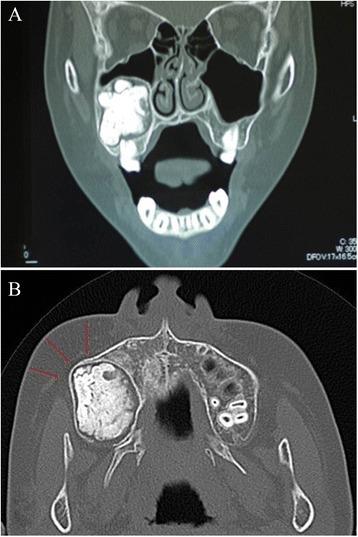

In 2013, an 11-year-old Japanese boy was referred to our department for a painless and large mass of the right maxillary region. A panoramic X-ray showed a unilocular cystic lesion in the right maxilla containing a calcified mass in the lesion associated with an impacted tooth. Computed tomography showed a cystic lesion that included calcified structures and measured 3.6×3.1×2.7 cm. In 2013, the patient underwent tumor extirpation combined with impacted tooth extraction. The histopathological diagnosis was an odontoameloblastoma. No recurrence was noted 27 months after the operation.

2013年,一名11岁日本男孩因右上颌区域无痛性巨大肿物被转诊至我科。全景X线片显示右上颌骨有一单房囊性病变,病变内有一钙化肿物,与一颗阻生牙有关。计算机断层扫描显示一个包含钙化结构的囊性病变,大小为3.6×3.1×2.7厘米。2013年,患者接受了肿瘤切除并拔除了阻生牙。组织病理学诊断为牙源性成釉细胞瘤。术后27个月未发现复发。